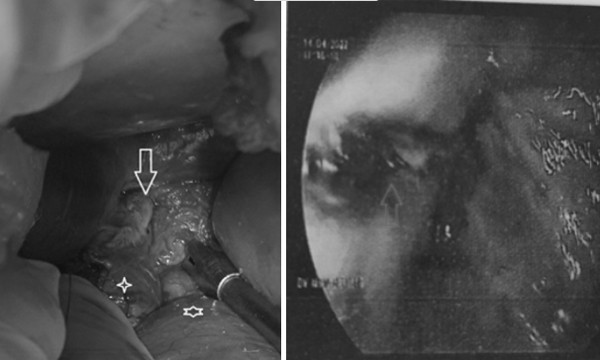

Phẫu thuật mở ngực trái ghi nhận góc tâm hoành trái nhiều giả mạc trắng, tụ dịch đục, khối viêm dạng đám quánh ở trung thất sau bọc thực quản kéo dài một đoạn 20cm từ cơ hoành đến ngang rốn phổi trái, tụ mủ đóng kén.

Ê-kíp bóc tách, mở rộng, rửa ổ áp xe và đặt vào khoang lồng ngực hệ thống tưới rửa cùng với ống dẫn lưu màng phổi trái.

Kết quả thám sát vùng bụng thấy bụng bệnh nhân sạch nhưng quanh thực quản bụng và tâm vị bị bầm. Bơm chất chỉ thị màu, bác sĩ ghi nhận nam bệnh nhân có đường rách thực quản dài 3cm.

Bệnh nhân đã được phẫu thuật khâu lại lỗ thủng thực quản, đắp một phần mạc nối lớn lên đường khâu. Anh cũng được đặt thêm 2 ống dẫn lưu bên cạnh phải - trái thực quản bụng và được mở dạ dày nuôi ăn.